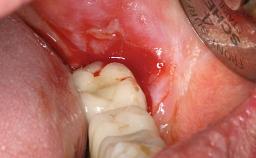

A 77-year-old male patient was referred for the management of frequent and repeated acrylic fracture of his existing mandibular fixed full-arch implant-supported metal/acrylic prosthesis. He also complained about softtissue soreness and the lack of retention and stability of his maxillary removable partial metal/acrylic prosthesis. Both prostheses had been delivered two years previously as part of his full-mouth rehabilitation (caries, tooth wear, tooth fracture). His medical history revealed high blood pressure, controlled with the use of antihypertensive medication.

Soft Tissue Grafting None

Soft Tissue Anatomy Intact Defective

Periodontal Status History of periodontitis or genetic predisposition